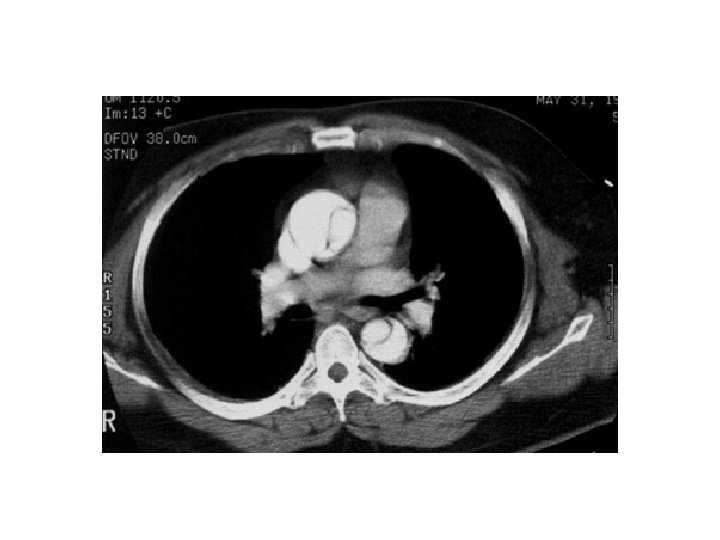

Typ B-dissektion med upphört flöde i nedre kroppshalvan (samma pat)

Samma patient 8 månader senare, efter thorakal stentning Trombotiserat falskt lumen Pat behandlad med TEVAR Stent vä njurartär Stent vä iliaca comm Stent hö iliaca ext Hö hemicolektomi